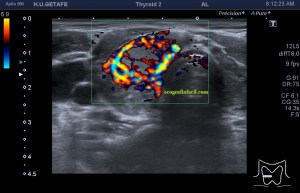

Era un nódulo hiperecogénico en el contexto de la tiroiditis en el estudio de una ecografía tiroidea.

Te enseño las imágenes, típicas de una exploración tiroidea de protocolo con semiología de tiroiditis.

De la imagen 1 a 7 el protocolo habitual, el estudio particular del nódulo con medidas y aplicación del doppler demuestra el aspecto típico del Caballero Blanco.

De la 8 a la 11 estudio con Doppler.

Resumen de las imágenes que has visto en el caso de hoy:

1. Hipoecogenicidad del parénquima

2. Heteroecogenicidad

3. Múltiples nódulos hipoecoicos muy pequeños

4. Doppler Color y Doppler Power aumentado de tamaño en el nódulo

Este es el aspecto ecográfico descrito anteriormente de la patología que habitualmente puede albergar el nódulo del que trata hoy el post y que no es otra que la de la Tiroiditis de Hashimoto.

El Caballero blanco, recibe el nombre debido a su semiología hiperecogénica, homogénea y solitaria circunscrito en la patología referida con anterioridad, puede aparecer en esta patología de forma benigna o degenerar en otro tipo de patología a formas malignas como el linfoma tiroideo.